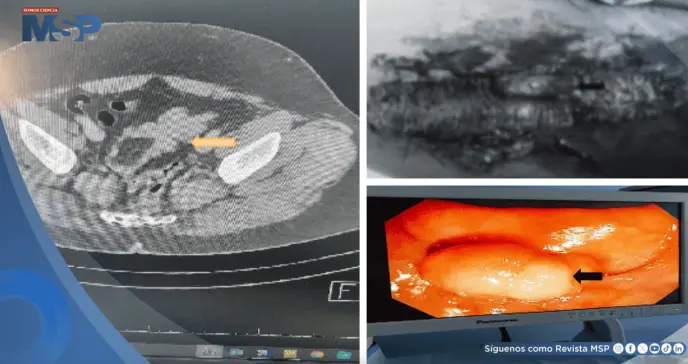

Se le realizaron exámenes de laboratorio, cuyos resultados estaban dentro de los límites normales. No se le realizó ecografía abdominal, pero sí se sometió a una tomografía computarizada a través de la cual se identificó una invaginación colo-colónica sigmoidea (condición en la que una sección del intestino grueso se dobla sobre sí misma, causando una obstrucción intestinal) con un punto de entrada.

La inflamación era 5 × 3,6 × 2,50 cm, con posibilidad de lipoma y, además, se realizó una colonoscopia que mostró una lesión pediculada blanquecina en el sigmoide que mide aproximadamente 3 × 5 cm.